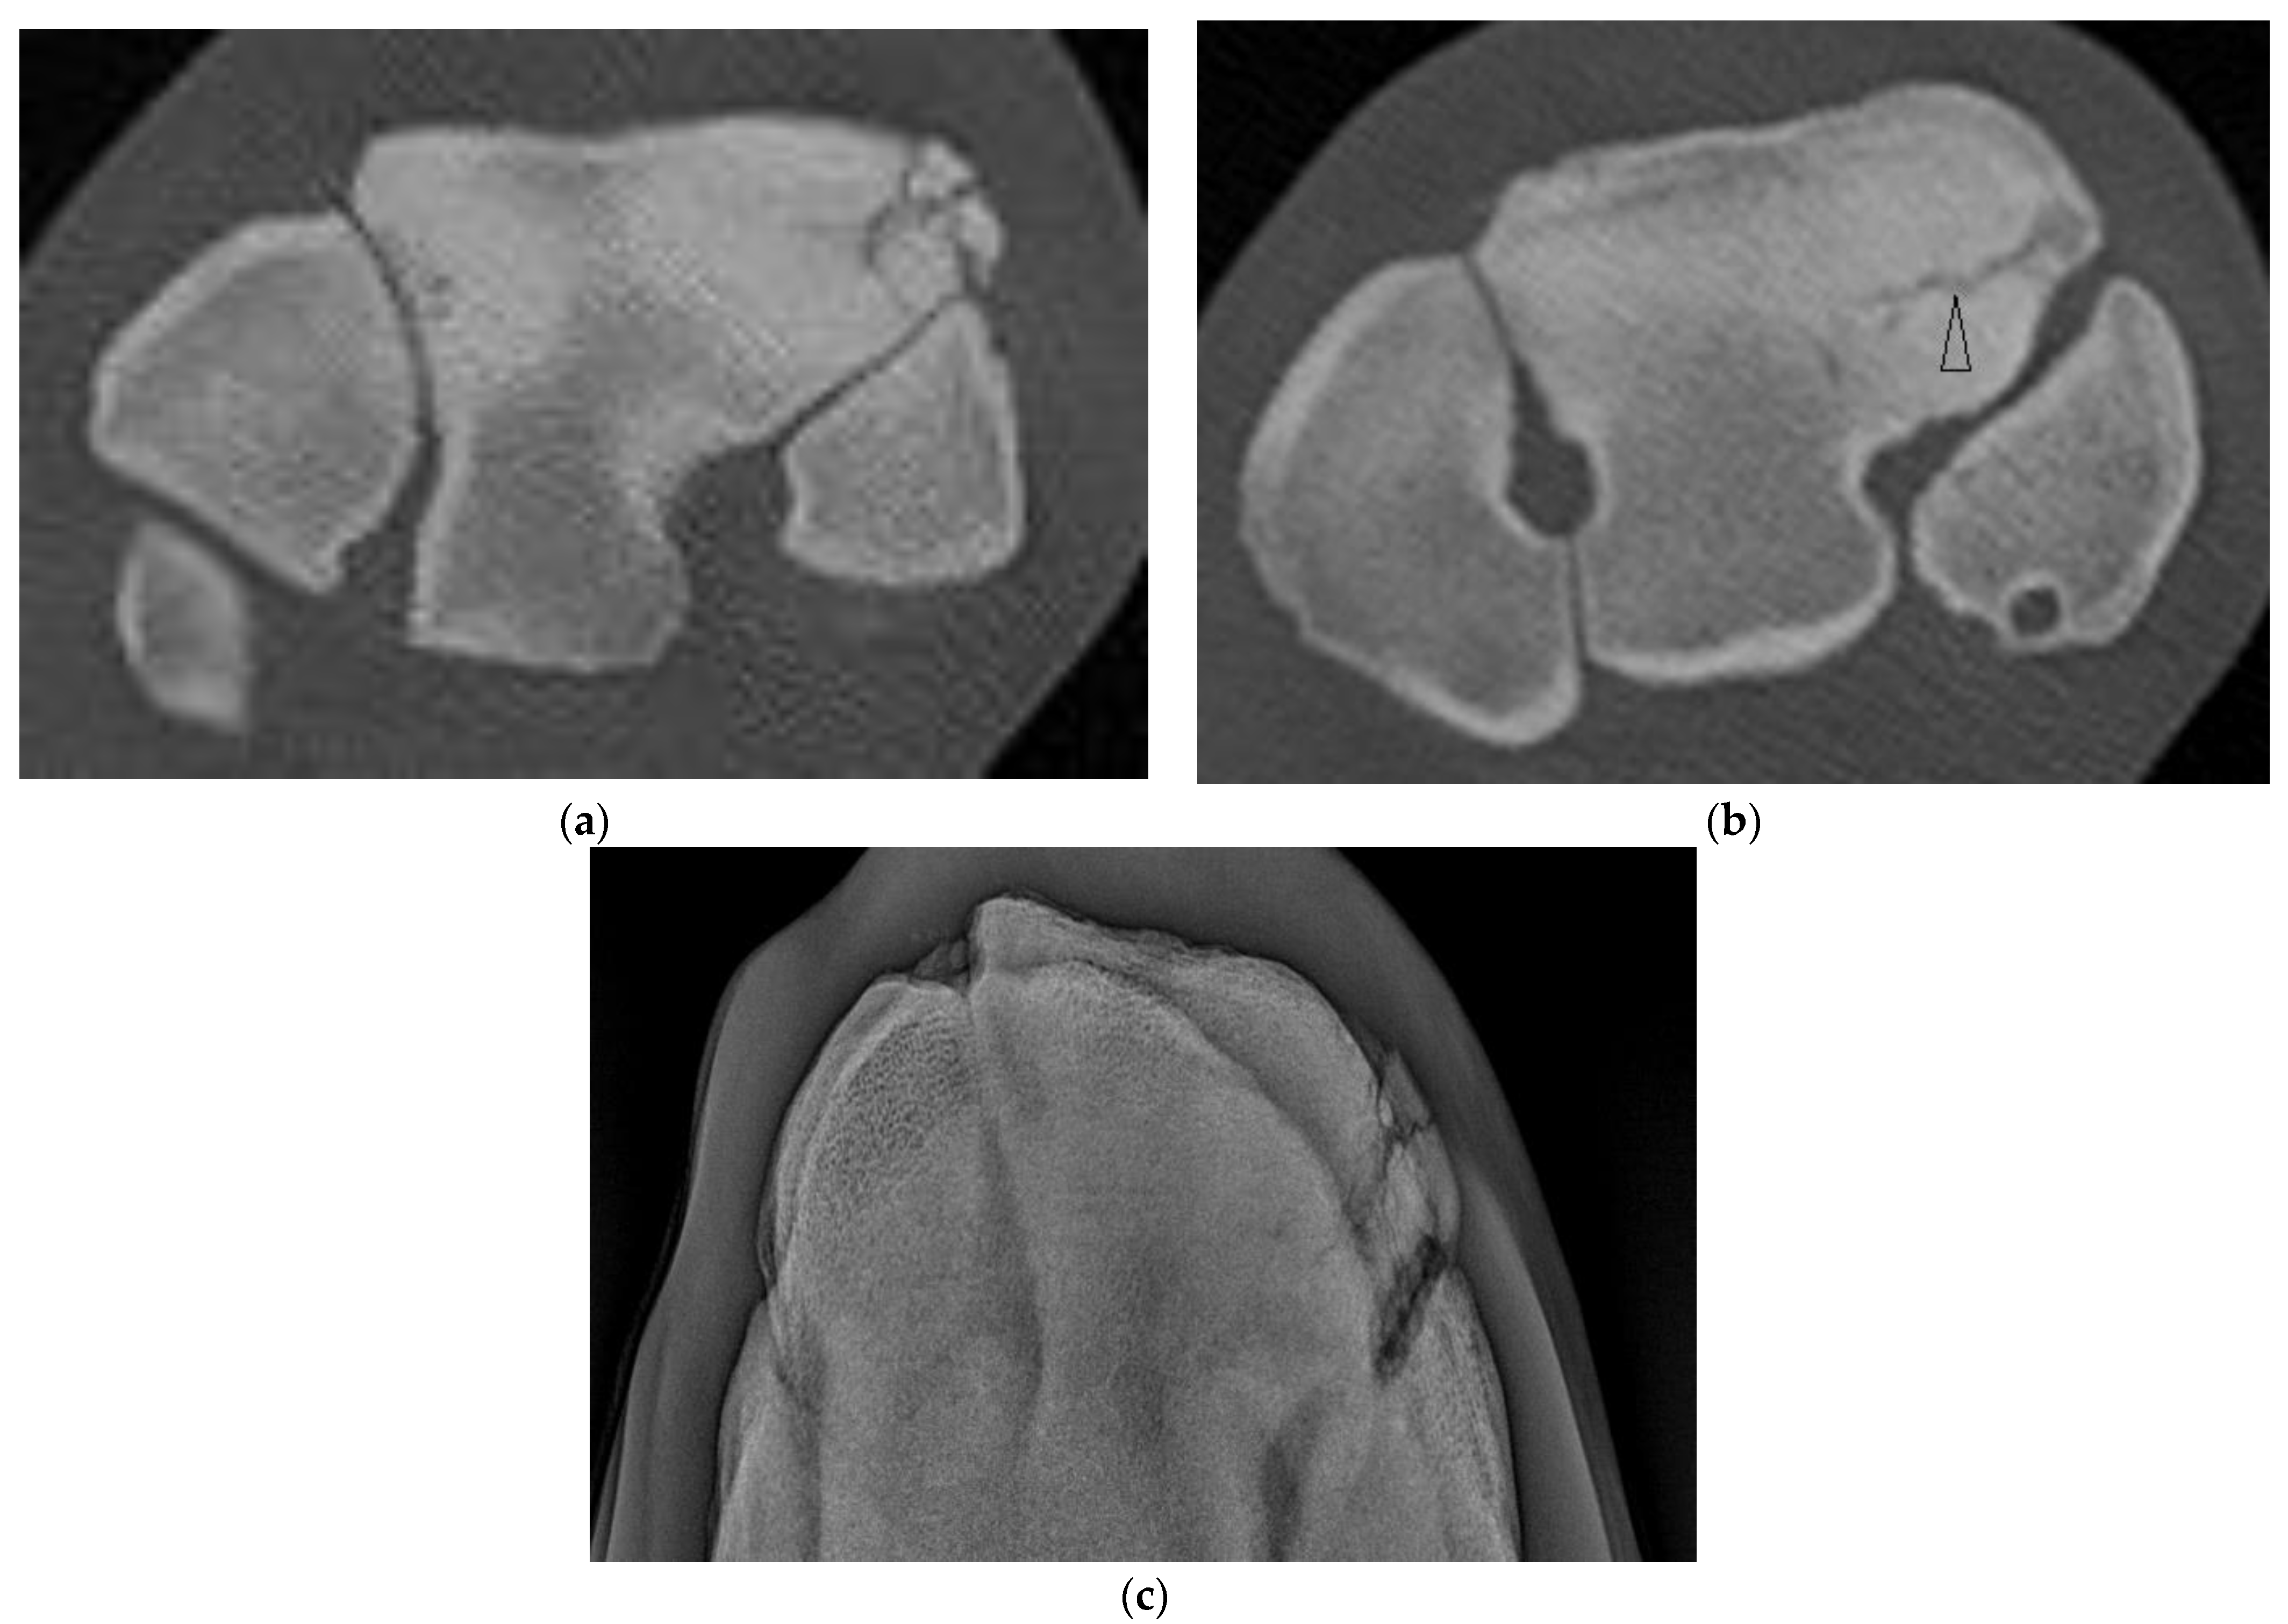

Of the five horses with incomplete, frontal, RaF Fx, one was not evident radiographically and CT was performed due to undiagnosed carpal lameness. On DR of this horse, severe sclerosis of the dorsomedial aspect of the RaF, mild modelling of distal dorsal aspect of Cr and mild entheseous new bone (‘carpitis’) of Cr were reported. CT revealed a subtle, linear, frontal radiolucency within the dorsomedial aspect of the RaF, modelling or osteophytosis (OP) at the C2-C3 articulation and changes within Cr (Figure 2, Supplementary Figure S2). Marked sclerosis was also a feature of the other cases, as were DCL that were more evident on CT than DR (Supplementary Figure S3) and/or mild entheseous new bone Cr, and additional lesions including OF of distal Cr (diCr) and SCBL with vague vertical lucencies that extended into the trabecular bone of diCr not detected on DR (Figure 2).

Figure 2. Images of the left carpus of a 3-year-old thoroughbred colt. (a) Flexed dorsoproximal-dorsodistal oblique radiographic view of the distal row of carpal bones. There is moderate sclerosis of the radial facet of the third carpal bone (C3). (b) Transverse and (c) sagittal CT images of the left carpus reveal an incomplete frontal fracture of the radial facet (arrow heads) that was not evident radiographically. (d) Within the radiocarpal bone there is a subchondral lucency approximately 4 mm from the dorsal articular margin, vague vertical lucencies that extend into the trabecular bone (arrows) and surrounding sclerosis.